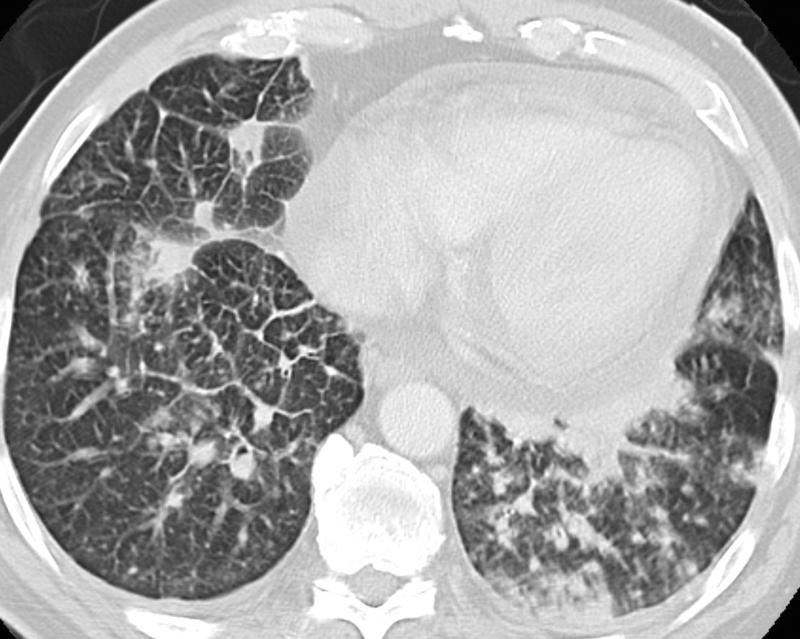

Gallery Lung Cancer Mets RCC b

RCC b